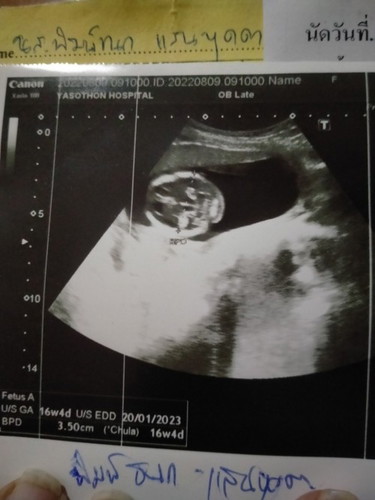

ภาพอัลตร้าซาวด์

ช่วยดูหน่อยค่ะ นี่คือหน้าน้องเหรอคะ

หัวค่ะแม่ ดูจากกลางหัวลงไป หมอจะซาวด์ดูสมองกับวัดขนาดหัวเด็กค่ะ

หัวน้องค่ะ น่าจะส่วนสมอง

หัวน้องค่ะแม่